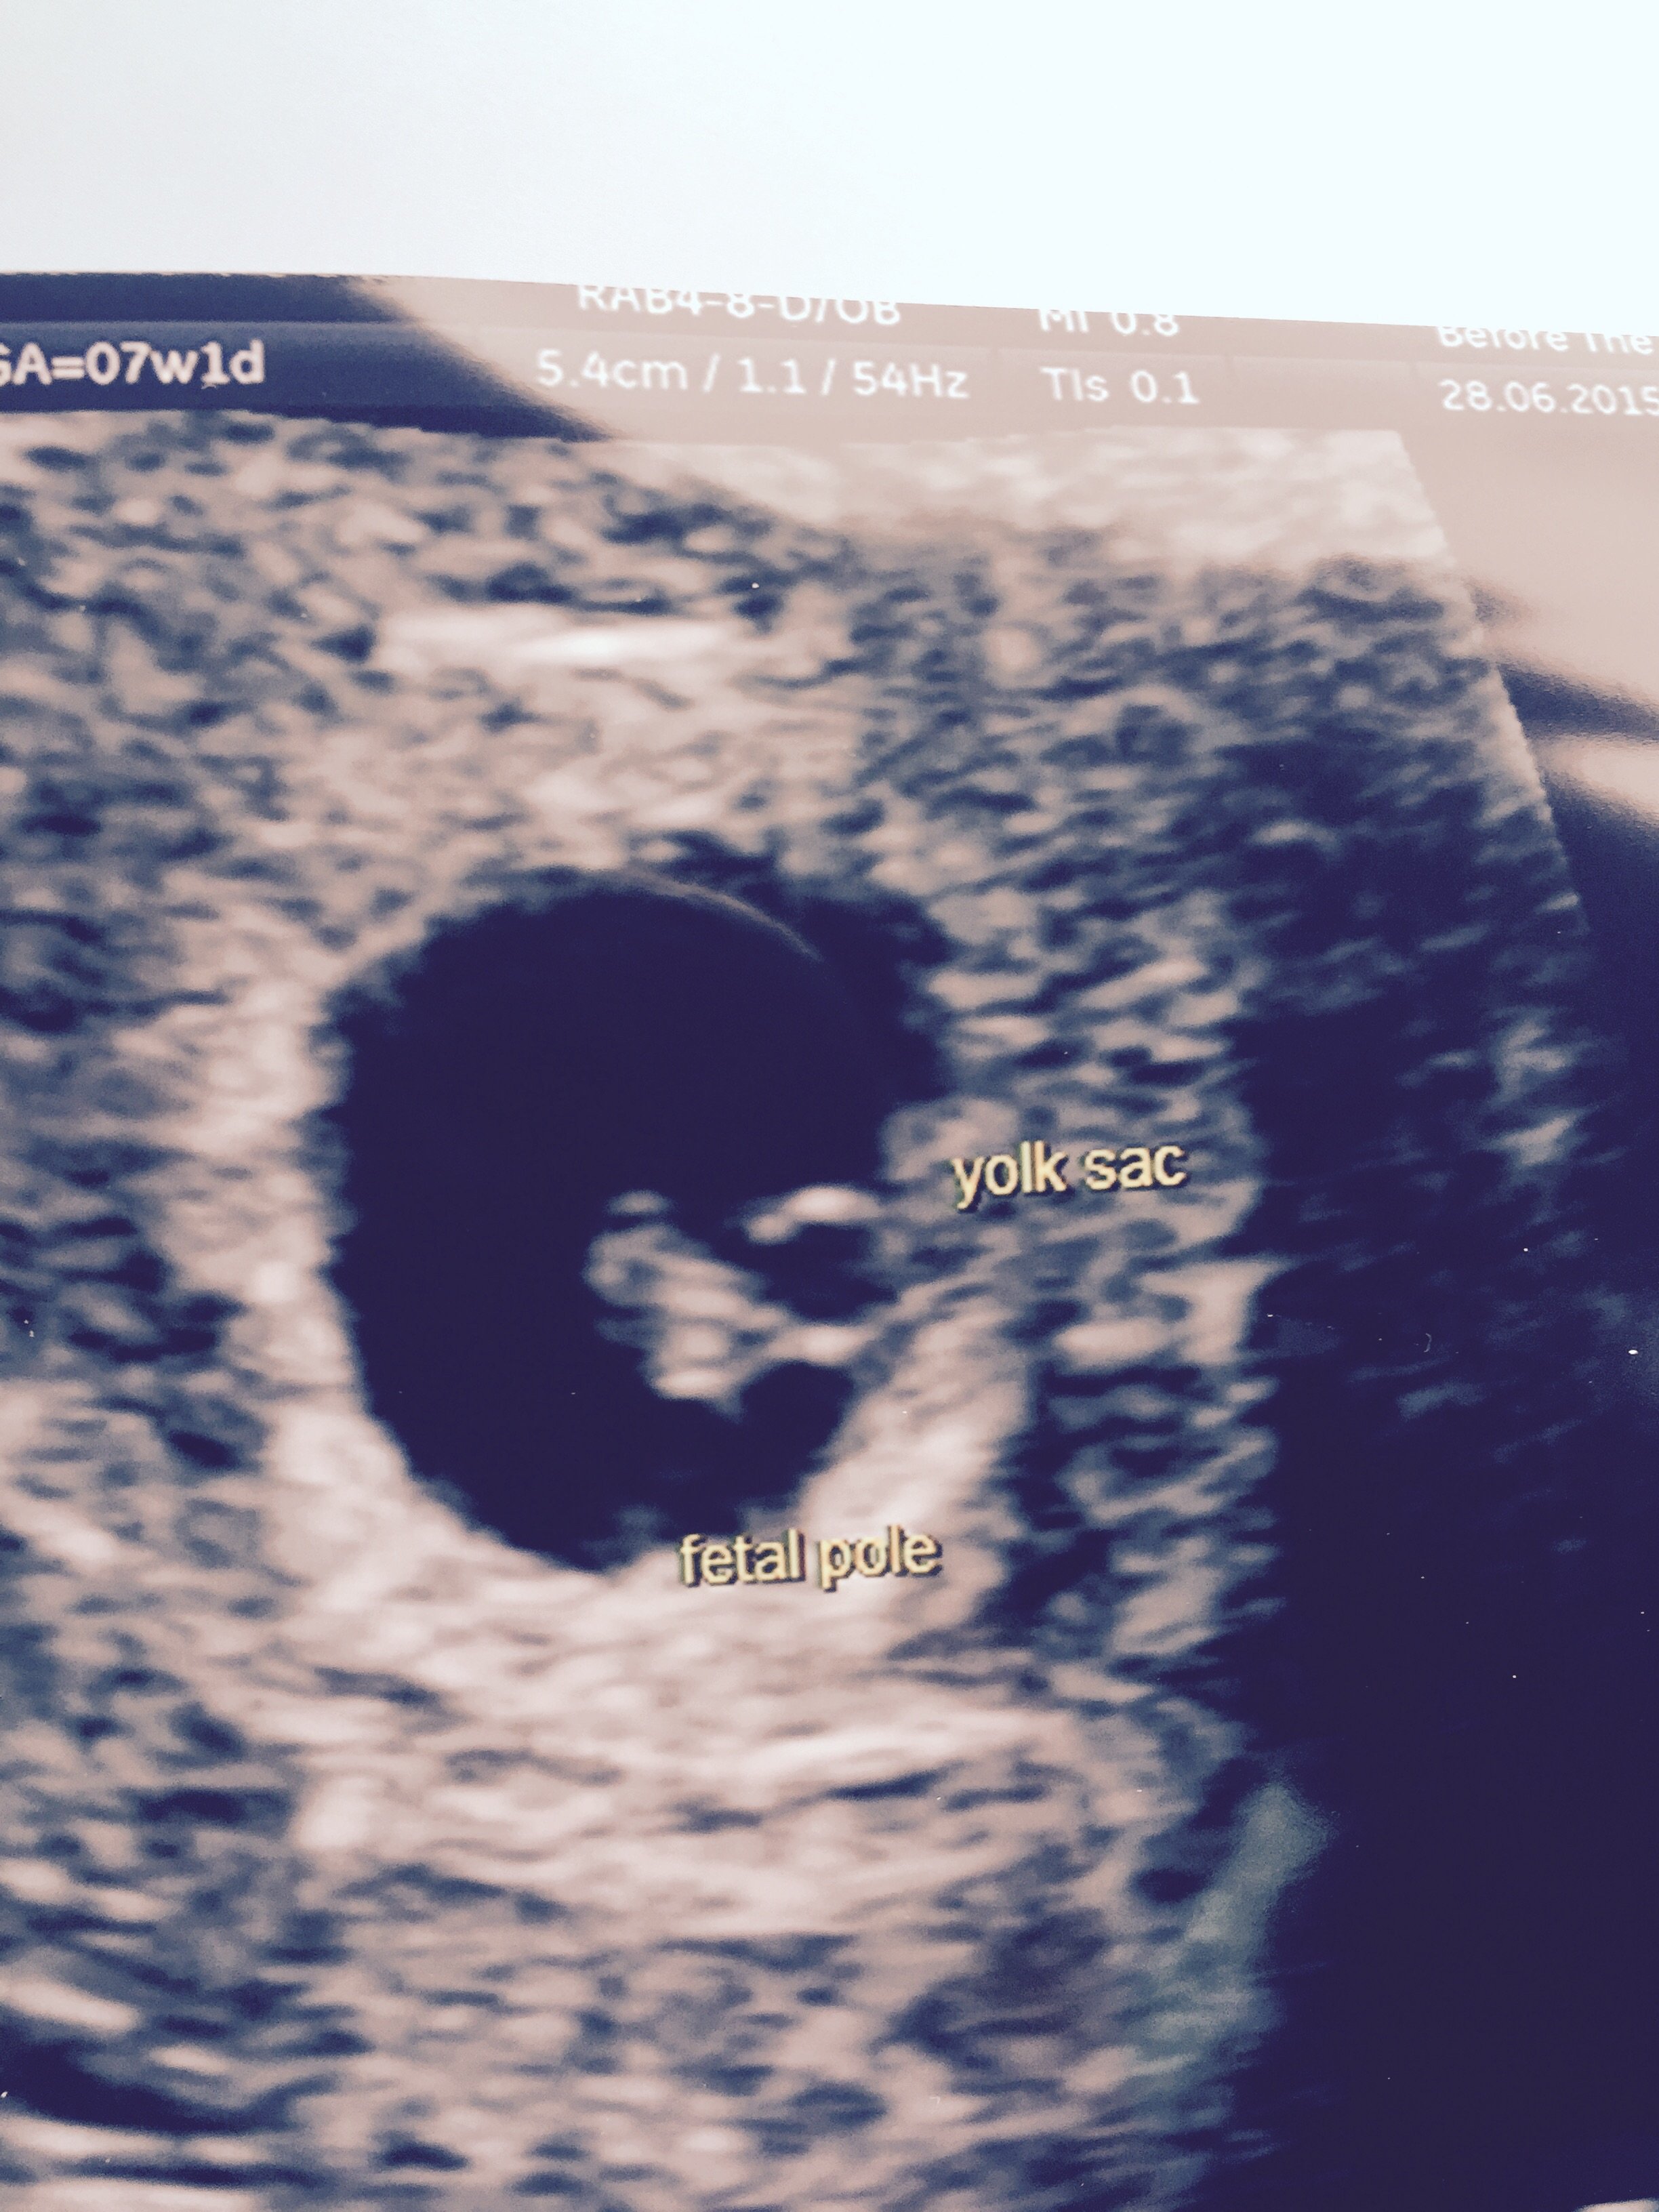

• Hi ladies, just an update! Been for my scan and I'm a fraction earlier than I thought so no heartbeat but a real clear yolk sac, had an internal but all was absolutely fine! I've a heammorage showing on one of the walls which explains the bleeding, they said they weren't worried it was just bruising or something similar. Have to go back two weeks today to check again that all looking good but here's the pic, great to see it!